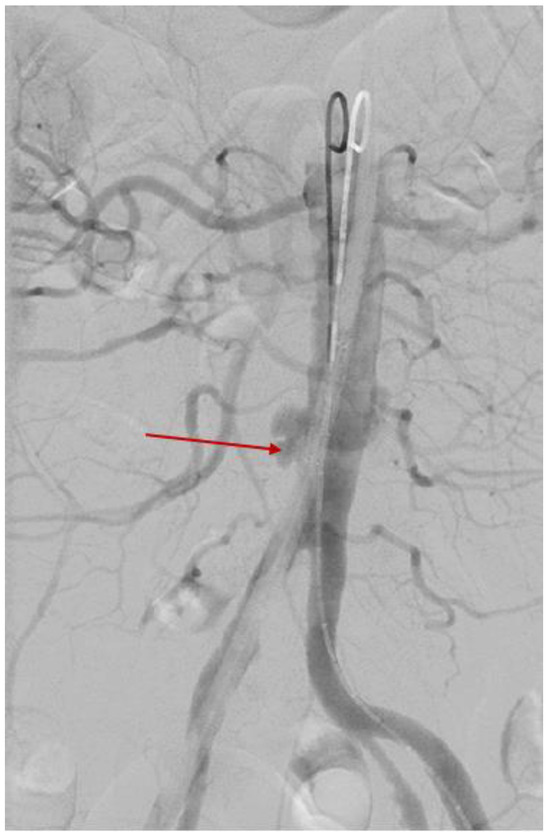

3.2.4. Minimally Invasive Surgery

3.2.5. One-Month Post-Surgery Follow-Up